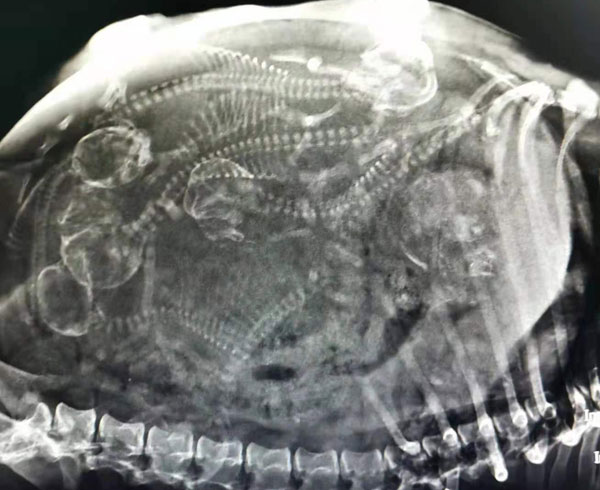

擁有專業的寵物醫生和先進的動物醫療設備,診療案例共同見證